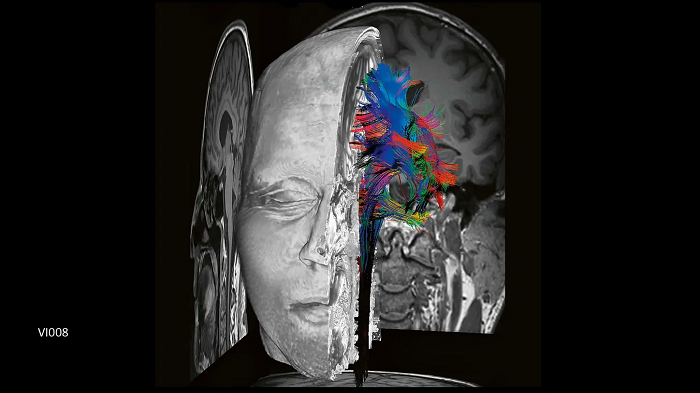

DTI fiber tracking 64 directions, post-processed with Neuro 3D

Image Credit: Siemens Healthineers